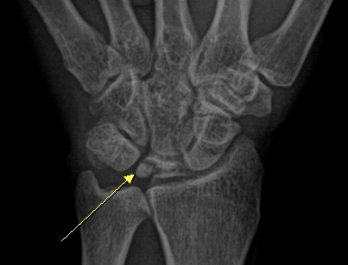

舟月骨缺血性坏死

腕关节发生骨缺血坏死的常见部位为舟骨和月骨

好发于20-30岁手工劳动者,也常见于腕部急性创伤和月骨骨折脱位后

男性多见

X线表现为病变早期骨形态尚可,骨质密度增高,其内可见囊样透亮影,进展期骨质塌陷,周边关节间隙增宽;MR对早期骨缺血坏死较敏感

舟骨缺血性坏死

54Y,M 月骨缺血性坏死